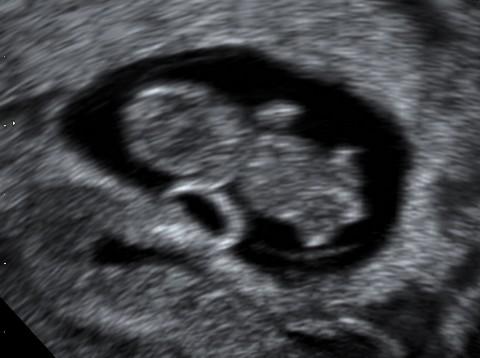

Na snímku je vidět plod se žloutkovým váčkem. Stáří plodu je 8 týdnů a 3 dny, velikost 19 mm. U plodu je snadno k rozeznání hlavička, horní a dolní končetiny, mezi nimi část pupečníku.